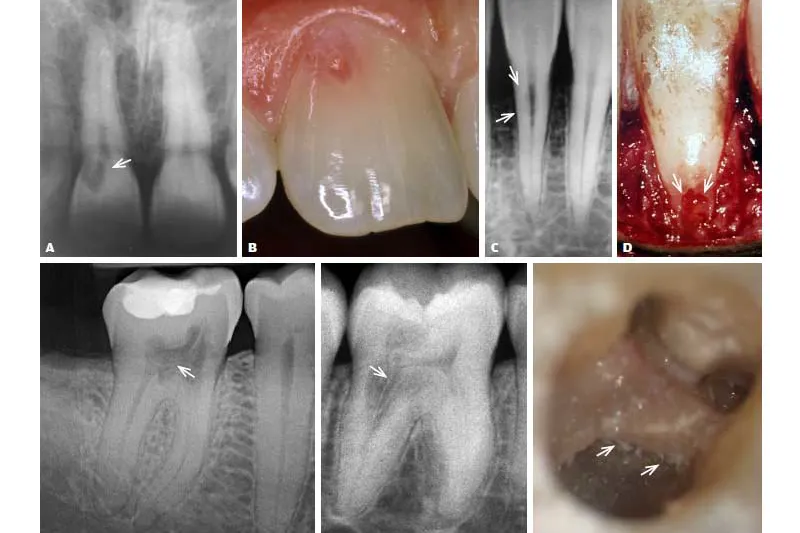

En hyppigt anvendt konventionel radiologisk klassifikation med fire progressionsstadier af cervikale resorptionsskader (Klasse I-IV, ad modum Heithersay) anvendes i denne artikel. Der er dårligere prognose, jo mere omfattende de resorptive skader er.

Fire tilfælde af cervikal resorption med stigende kompleksitet svarende til Heithersays klassifikation præsenteres, og hvor endodontiske og kirurgiske behandlingsprincipper benyttes. Ved de fremadskridende stadier er rodbehandling nødvendig udover behandling af resorptionskaviteten.

Endodontiske og kirurgiske behandlinger af cervikale resorptioner ad modum Heithersay gennemgås. Det er behandlingsforløb over flere seancer, og ikke sjældent skal en pulpektomi udføres af tekniske grunde, fordi den invasive cervikale resorption kan omslutte rodkanalen fuldstændig. Behandlingerne bør ske under brug af forstørrelse. En realistisk vurdering i almen praksis vedrørende behandling af cervikal resorption er, at den bør begrænses til Klasse I og II (ad modum Heithersay) og med anbefaling af, at den er understøttet af en CBCT-undersøgelse. Såfremt man ikke arbejder under forstørrelse, bør henvisning foretages og ikke mindst ved Klasse III og IV. En aflukning af overfladebruddet og fjernelse af det resorptive væv er afgørende for et godt resultat. Cervikale resorptive læsioner kan have forskellige progressionshastigheder, hvilket understreger vigtigheden af kontinuerlig kontrol, både før og efter behandling.